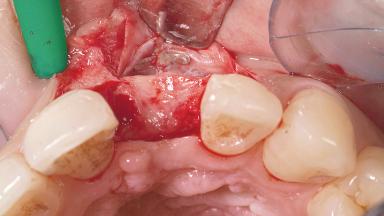

Late Placement of an Implant in a Maxillary Left Central Incisor Site

A 30-year-old female patient had lost tooth 21 and was referred to our clinic for consultation and treatment. Due to advanced apical infection, tooth 21 had been extracted two months earlier at another clinic and an acrylic-resin tooth had been bonded to the adjacent teeth. The patient desired implant treatment to avoid any damage to the adjacent natural teeth. While the patient had no history of any systemic disorder, she was a heavy smoker and exhibited medium to advanced periodontitis in the entire jaw. After the initial treatment to achieve a pocket probing depth of less than 4 mm and no bleeding on probing, a decrease in the height of the papillae mesial and distal to the extraction site and overall gingival recession were observed.